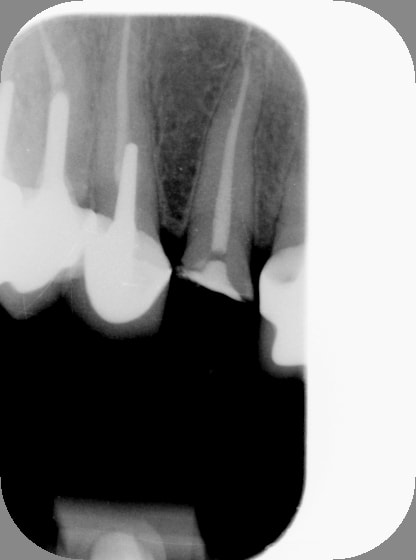

Pour la forme...il y a 15min...

Radio2 xuf6ph - Eugenol

Radio grxbfa - Eugenol